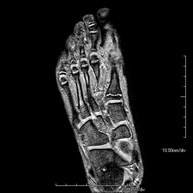

- RM Pie

Exploración para el estudio de lesiones en tendones músculos y pequeñas articulaciones. Permite valorar con eficacia las lesiones en el cartílago. También es de mucha utilidad para completar la exploración ecográfica previa. No emplea radiación ionizante. Tiene una duración aproximada de 20 minutos.